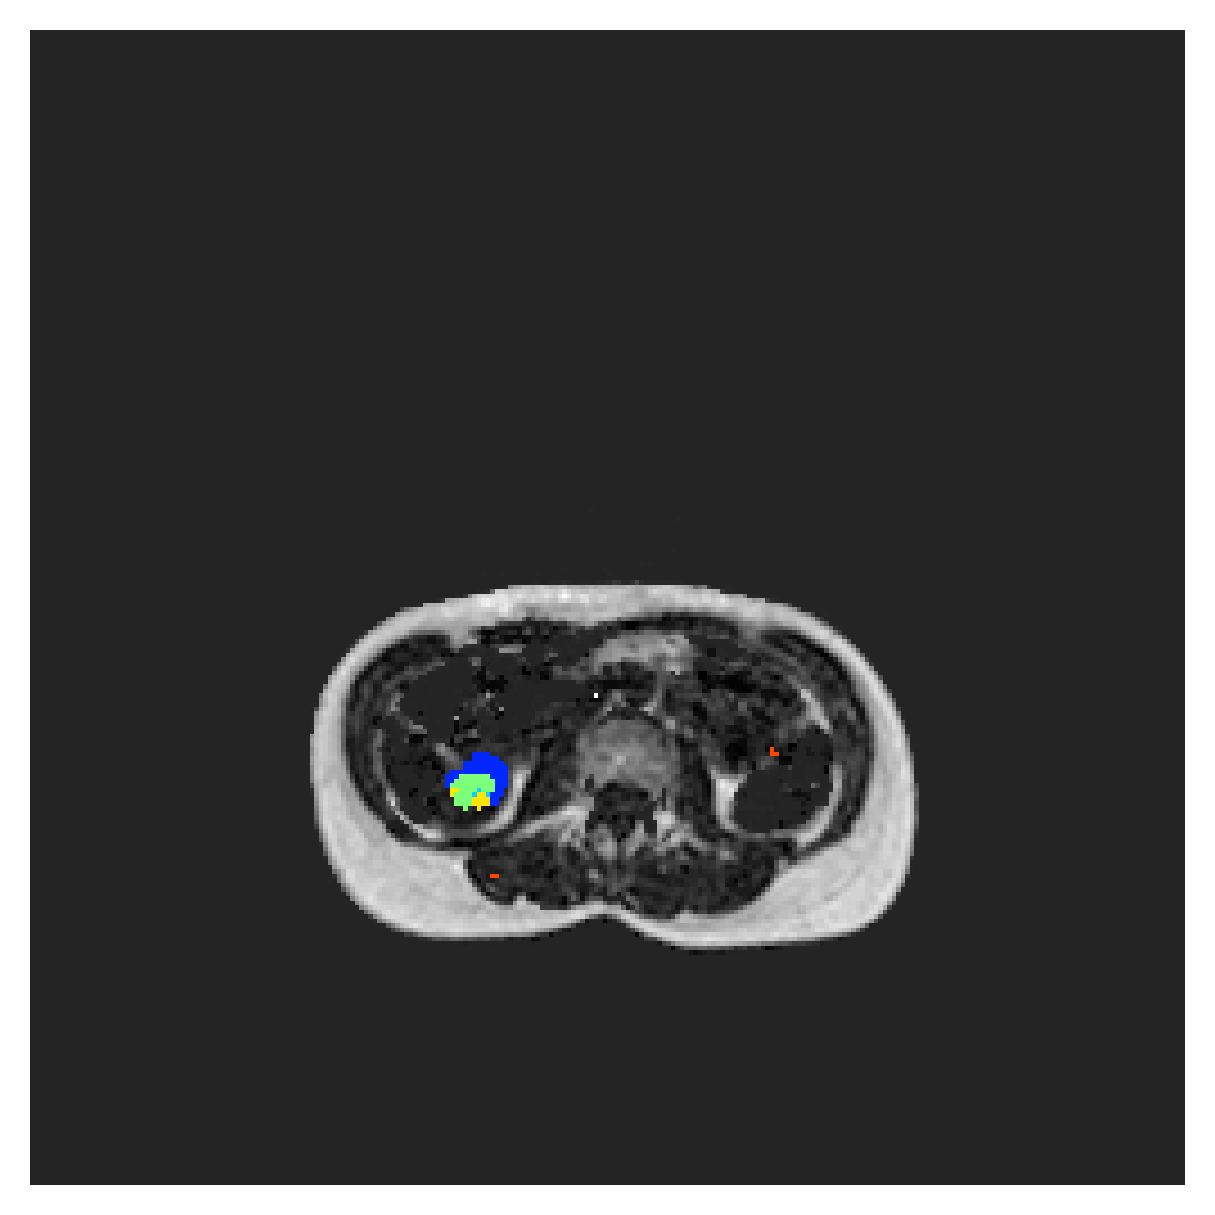

5.2 Abdominal organ segmentation

Using 2D distance maps

In Table 3, the average DSC and HD95 results are shown (both using 2D and 3D distance maps) for the task of abdominal organ segmentation in POEM data (for boxplots see figures 8 and 9). We see that training with and (with distances calculated on 2D slices) performs comparably, while using and produces lower scores in both DSC and HD95 metric. On this dataset, the CRF-loss is able to compete with the boundary loss-based training strategies, even outperforming them on most classes. Most notably, all models trained with boundary loss appear to have a hard time segmenting the liver. We hypothesize this may be due to extremely severe class imbalance, as the liver covers a very large area compared to the rest of the classes. It is thus also more strongly affected by undersegmentations.

Using 3D distance maps

Inspecting the values of training with on distance maps computed in 3D from Table 3, we notice that the results generally improve over values achieved by using 2D distance maps. Most notable decreases are visible in HD95 values, as using volume-calculated distance maps provides more global information and additionally penalizes spatially unreasonable segmentations. The methods based on are now able to compete with the CRF-loss, in particular the one.

In Figure 10, the validation curve evolution is plotted. Comparing it to the one with using 2D-computed distance maps, in Figure 7, we see that the curves for all the methods training with improve, with the exception of based one. The lack of improvement here could be attributed to the MBD bleeding through object boundaries (due to noise) and propagating low distances further away in the volume, causing under-penalization. This is also suggested by the degradation in performance from 2D to 3D maps in Table 3. But at the same time, it allows for better segmentation of large and/or elongated (homogeneous) objects, which is also confirmed by the large improvement of liver segmentation scores in Table 3.

5.2.1 Qualitative comparison

In Figure 11 and 12 we show the same random slices in cases of calculating the boundary loss on 2D- and 3D-based distances, respectively. Comparing the two figures again indicates that the intensity-aware distances offer most improvement when calculated in 3D over 2D. The exception here is the MBD, which seems to even slightly degrade for most classes.